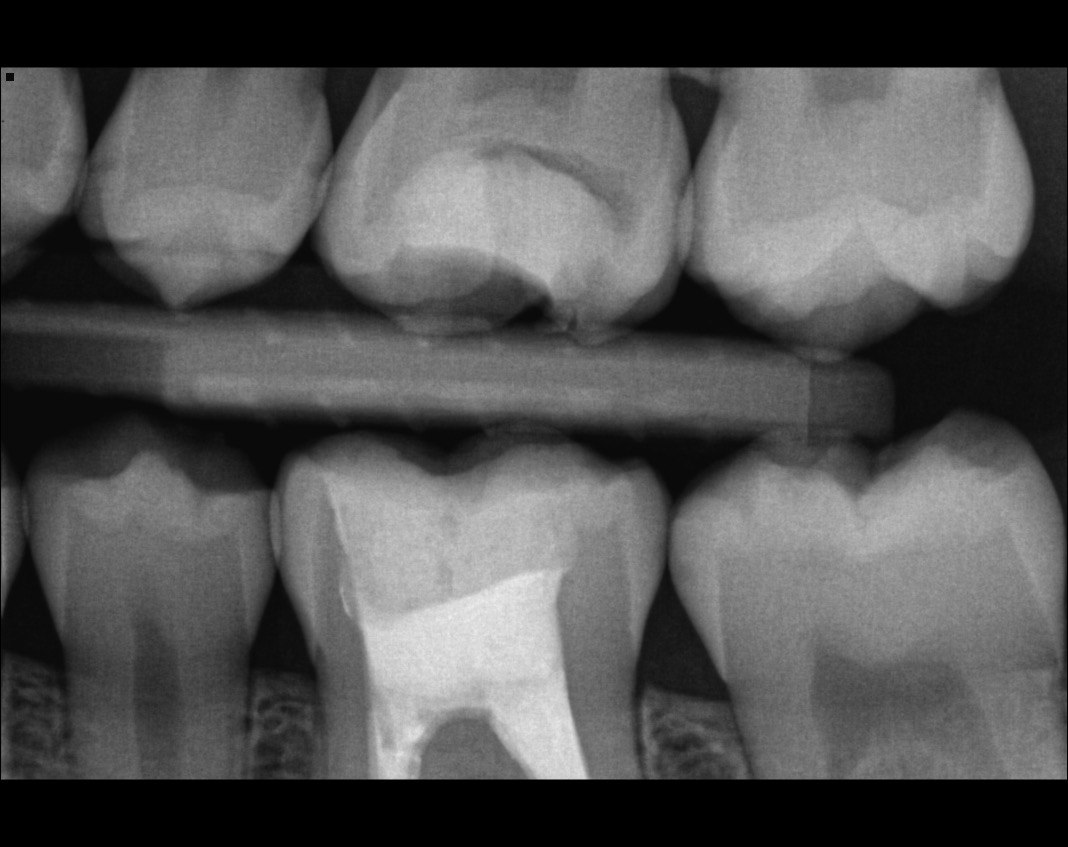

Question 5: Which surface shows recurrent caries?

Question 6: Which surface shows recurrent caries?

Question 7: What are the options associated with the distal surface of the tooth # 2.1 and mesial surface of the tooth # 2.2 respectively?

Question 8: What is the condition associated with the occlusal surface of the tooth # 1.6?

Question 9: What is the condition associated with the mesial and distal surfaces of the tooth # 1.4 respectively?

Question 10: What is the condition of the distal surfaces of the teeth # 1.5 and 1.6 respectively?